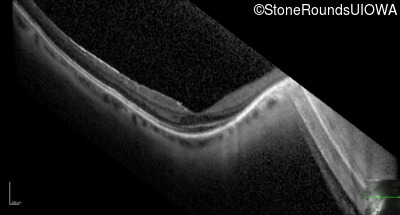

Optical Coherence Tomography - Right - 20/25 -3

Exemplar / OCT Stack